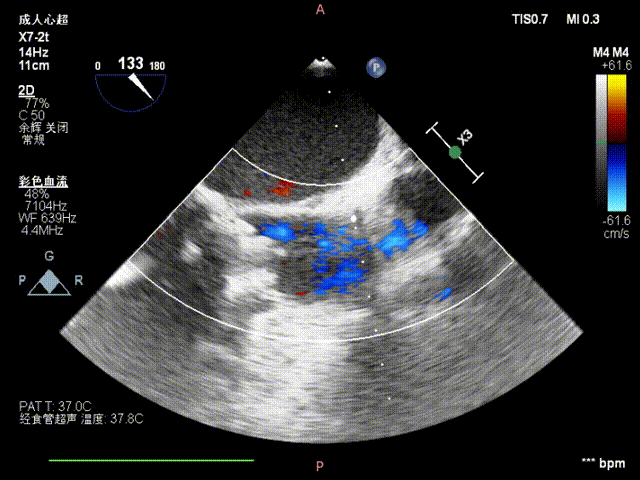

手术超声结果

主瓣

术前

术后

术前术后流速压差对比,术前最大速度464cm/s,平均速度316cm/s,最大压力梯度86mmHg,平均压力梯度46mmHg;术后最大速度254cm/s,平均速度151cm/s,最大压力梯度26mmHg,平均压力梯度11mmHg:

二尖瓣

术前术后流速压差对比,术前最大速度265cm/s,平均速度189cm/s,最大压力梯度28mmHg,平均压力梯度16mmHg;术后最大速度194cm/s,平均速度137cm/s,最大压力梯度15mmHg,平均压力梯度8mmHg: